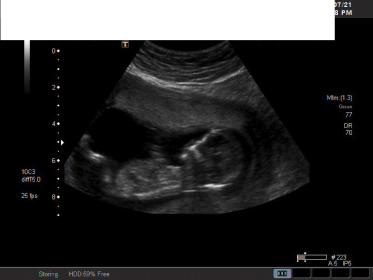

I haven't been on here for awhile. It became too much for me to think about this baby's gender everyday. I couldn't do it. It's so hard this GD. It reared up again today for our ultrasound. It's 14 weeks so I thought they would be able to guess - they didn't tell me anything. I don't even think I have any clear nub shots. Any guesses would be good - Why can't I see a nub!!! UGH....I hope everyone is doing well and getting the DG!!Attachment 26328Attachment 26329